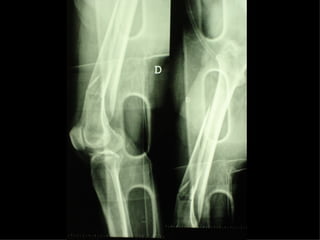

APPARATO LOCOMOTORE Hanno priorità assoluta  : Fratture esposte Fratture con lesioni vascolari e nervose Fasciotomie Fratture multiple delle ossa lunghe Fratture della colonna vertebrale

Fratture multiple delle ossa lunghe

Un’altra situazione di emergenza ortopedica è rappresentata dalle fratture delle ossa lunghe in pazienti con gravi traumi cranici e toracici